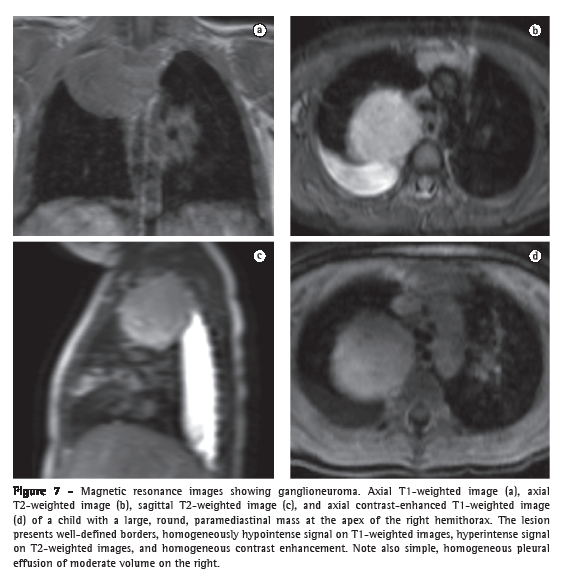

Neurogenic tumors are most commonly found in the posterior mediastinum, in the paravertebral region, and there is often a link between neurogenic tumors and the neural foramen (Figure 7). The lesions can originate from the peripheral nerve-being benign (neurofibroma and schwannoma) or malignant (neurofibrosarcoma)-or from the sympathetic ganglion (ganglioneuroma, ganglioneuroblastoma, and neuroblastoma). Benign lesions are more commonly characterized as spherical or lobulated masses with high T2 signal intensity, intense contrast enhancement, and homogeneous appearance, with the exception of neuroblastomas, which can be more heterogeneous and present with calcifications. Malignant lesions tend to be larger, more irregular, and more heterogeneous and present evidence of invasion of the medulla and thoracic spine.(57)